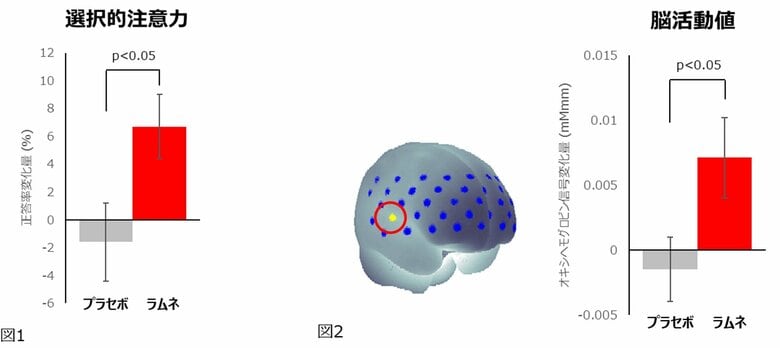

ラムネ摂取時はプラセボ摂取時と比較して、選択的注意力の指標であるフランカー課題の正答率が有意に上昇(図1)し、その時の脳血流(オキシヘモグロビン信号)が有意に増大(図2)しました。また、EACLの「エネルギー覚醒+」スコア(図3)とPOMS2短縮版の「活気‐活力」スコア(図4)が有意に上昇し、反対にネガティブ気分尺度である「怒り‐敵意」とTMDスコアが有意に低下しました。

この結果から、ラムネを摂取することによって認知テストにポジティブな気分で集中して取り組み、脳の一部の機能の活動が活性化することが示唆されました。本研究では集中して認知テストに取組んでいる時に脳の一部の活動が活性化していることを現象として捉えることができましたが、それらの関連性やメカニズムについては未解明な点も多く、今後の更なる研究が望まれます。